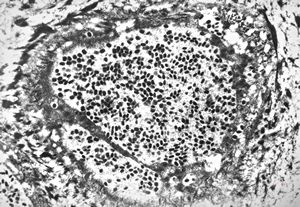

M,50y. | Pneumocystis carinii